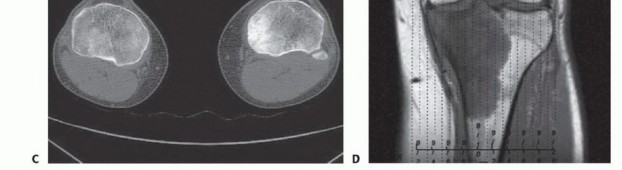

التصوير المقطعي المحوسب والتصوير بالرنين المغناطيسي

يُعد التصوير المقطعي المحوسب (CT) والتصوير بالرنين المغناطيسي (MR) أدوات لا غنى عنها لتحديد مدى تدمير القشرة العظمية، والامتدادات داخل النخاع العظمي، وامتدادات الورم في الأنسجة الرخوة المحيطة. هذه البيانات حيوية لتحديد مستوى استئصال قصبة الساق، والذي يكون عادةً 3 إلى 5 سم بعيداً عن منطقة إصابة الورم داخل النخاع.

يمكن للتصوير بالرنين المغناطيسي أيضاً الكشف عن "الآفات القافزة" (skip lesions)، وهي بؤر ورمية منفصلة عن الورم الرئيسي، والتي قد تؤثر على مدى استئصال قصبة الساق. يوفر الأستاذ الدكتور محمد هطيف تحليلاً دقيقاً لهذه الصور لضمان تحديد هامش جراحي آمن وفعال.

صورة شعاعية توضح ورماً عظمياً في قصبة الساق القريبة.

صورة شعاعية تظهر ورماً خلوياً عملاقاً في قصبة الساق القريبة.

صورة مقطعية توضح الورم الذي يملأ مشاش قصبة الساق القريبة.

صورة مقطعية أخرى للورم في قصبة الساق.

صورة شعاعية جانبية توضح ساركوما عظمية في قصبة الساق القريبة.

صورة بالرنين المغناطيسي تظهر مدى امتداد الورم داخل النخاع العظمي.

صورة شعاعية تظهر تدميراً قشرياً وامتداداً للأنسجة الرخوة للورم.

صورة مقطعية توضح تدميراً قشرياً وامتداداً للأنسجة الرخوة للورم.